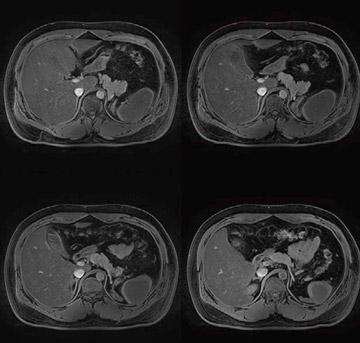

Vantage Titan 3Tは,送信RFコイルへの給電ポイントを4ポイントにし,位相と振幅をコントロールするMulti-phase Transmissionを使用することによって,躯幹部でも濃度ムラのない均一な画像が撮像可能になった(図4)。これにより,3T装置を日常ルーチン検査で躯幹部も含め幅広く使うことが期待できる。3Tのメリットである高いSNRを生かした高分解能撮像が期待できる。さらに,従来は実現困難であった非造影MRAも,躯幹部で使用可能になった(図5)。Time-SLIP法など最新撮像法との組み合わせにより,3Tのポテンシャルを引き出し新しい領域が拓かれるものと期待される。

図4 均一な腹部脂肪抑制画像